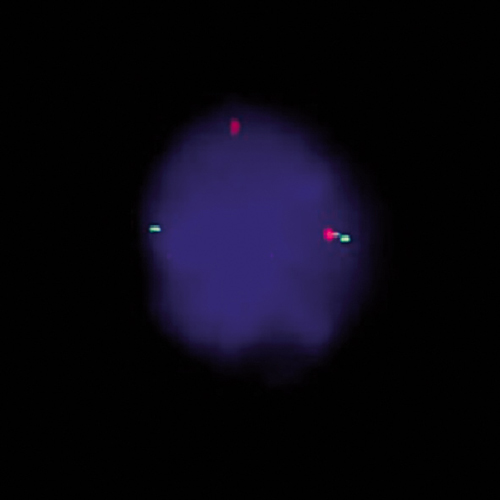

SS18 (18q11) Break probe hybridized to patient material showing translocation of the SYT (SS18) gene region at 18q11 (1RG1R1G).

The characteristic chromosomal abnormality in Synovial Sarcoma t(X;18)(p11.2;q11.2) is present in 90% of the patients. This translocation results in the fusion of the synovial sarcoma translocation, chromosome 18 (SS18) gene to either of two distinct genes, SSX1 or SSX2, located on the X chromosome. The SS18 (18q11) Break probe is optimized to detect translocations involving the SS18 gene region at 18q11 in a dual-color, split assay on paraffin embedded tissue sections.